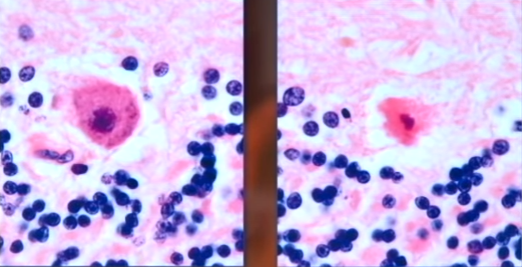

| Khi chụp bên trong hộp sọ của Kathleen, chuyên gia pháp y thấy một số tế bào thần kinh màu đỏ. Sự xuất hiện của chúng cho thấy nạn nhân đã hôn mê trong vài giờ trước khi chết. Do đó cảnh sát kết luận cái chết của Phó chủ tịch tập đoàn Nortel Networks là một vụ án mạng, chứ không phải tai nạn. Họ nghi Michael giết vợ, song nhà văn khẳng định ông rất yêu Kathleen và không bao giờ làm hại bà. |